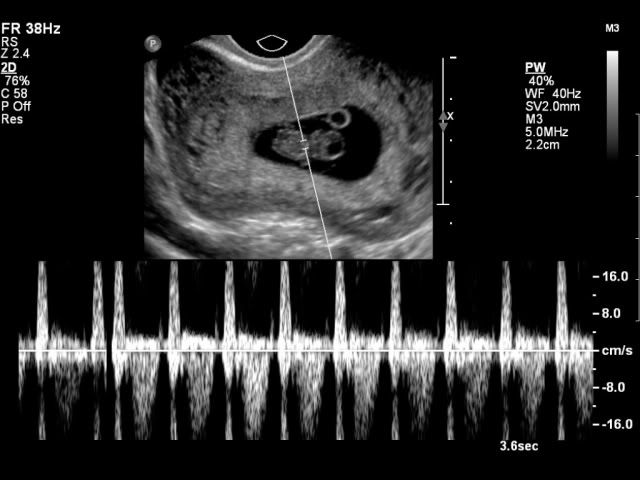

Presenting Jacob, my grandson. In about 6 weeks, I will get to hold him, and kiss him and love him.

This was from over 10 weeks ago. Little Baby-boo has grown considerably. Unless something accidently shows up, we will not know the sex until the birth. Next week will be half way marl.

This was from over 10 weeks ago. Little Baby-boo has grown considerably. Unless something accidently shows up, we will not know the sex until the birth. Next week will be half way marl. -